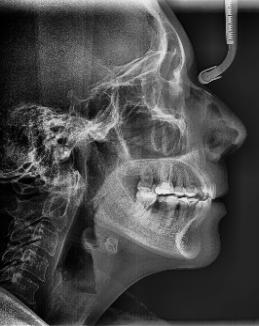

Estudios radiográficos de inicio

En la radiografía lateral de cráneo (Figura 4) se ve la aparatología con la que llegó la paciente, el perfil es convexo, hiperdivergente y las vías aéreas permeables.

En la radiografía panorámica (Figura 5) se observan en 20 dientes los brakets viejos, en los molares 16, 27 las bandas, el canino 13 retenido en el paladar, el botón de Nance, la

ausencia de molares 26, 46. Elmolar 16 tiene un tratamiento endodóntico

Figura 3. Oclusal superior e inferior. Figura 4. Radiografía lateral de cráneo de inicio.

radiografía lateral de cráneo la mejoría en la inclinación del incisivo inferior.